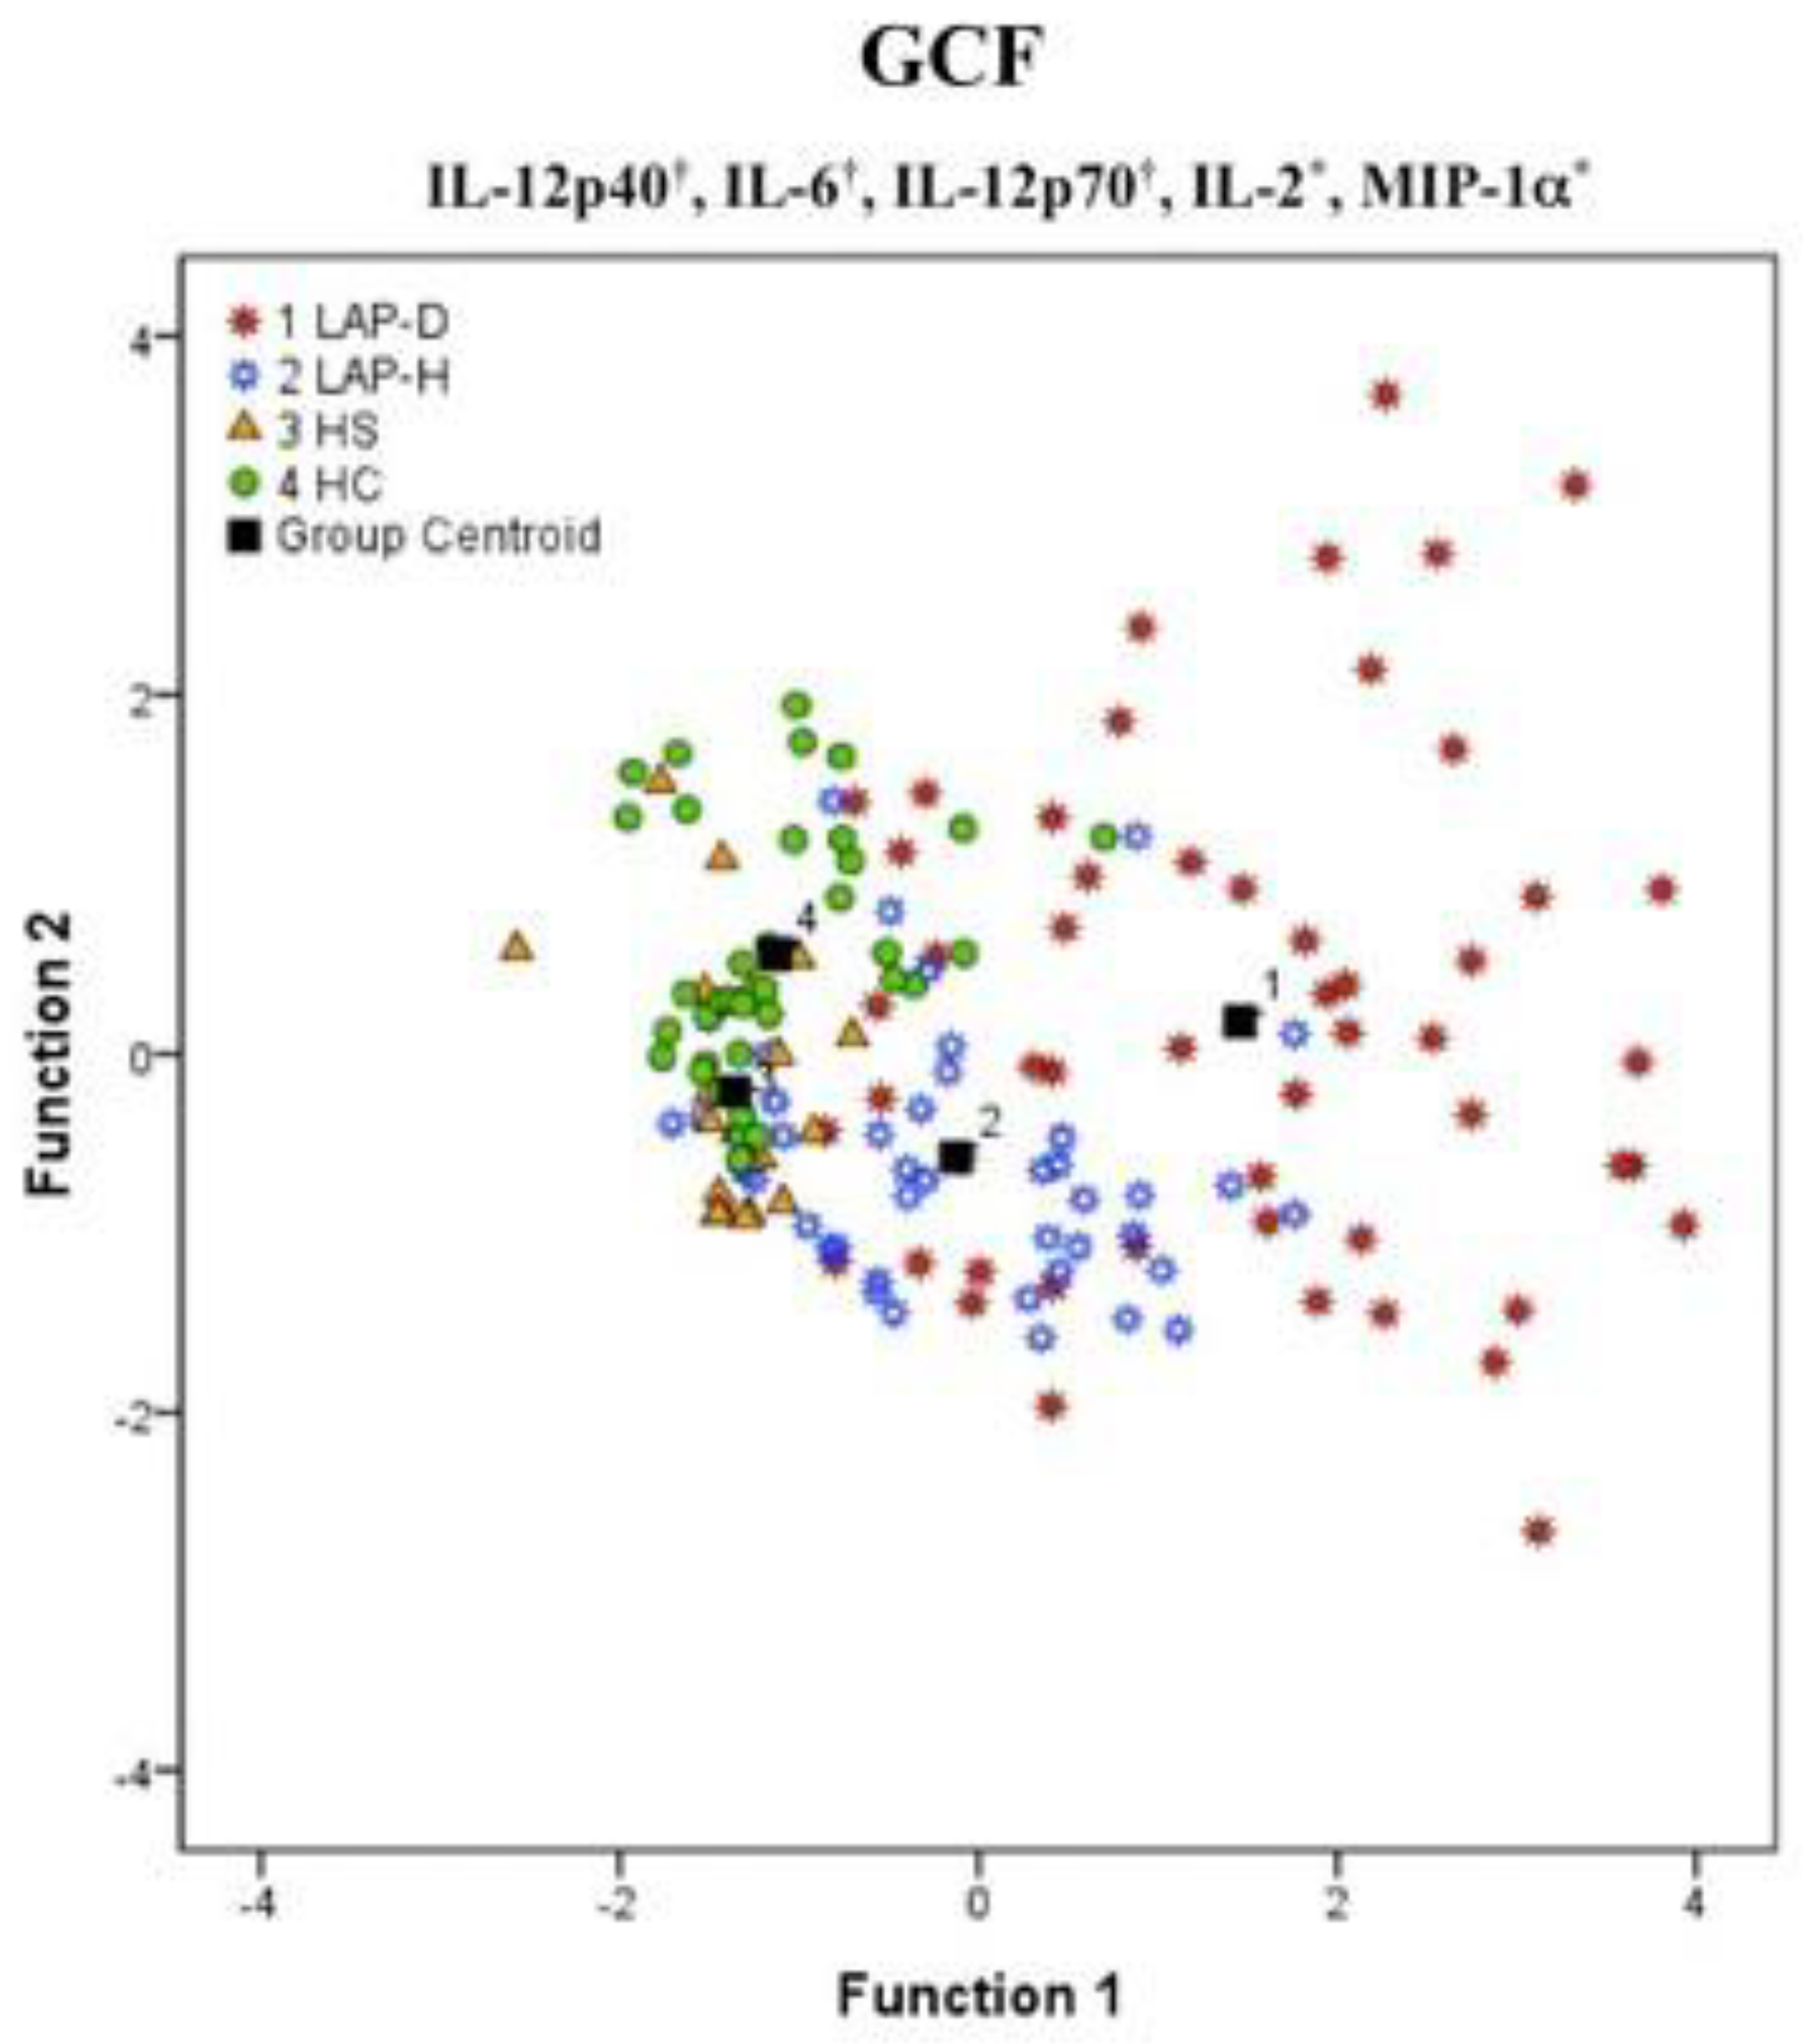

2. Immunological Aspects

- Branco-De-Almeida, L.S.; Cruz-Almeida, Y.; Gonzalez-Marrero, Y.; Huang, H.; Aukhil, I.; Harrison, P.; Wallet, S.M.; Shaddox, L.M. Local and Plasma Biomarker Profiles in Localized Aggressive Periodontitis. JDR Clin. Trans. Res. 2017, 2, 258–268. [Google Scholar] [CrossRef] [PubMed]

- Shaddox, L.M.; Wiedey, J.; Calderon, N.L.; Magnusson, I.; Bimstein, E.; Bidwell, J.A.; Zapert, E.F.; Aukhil, I.; Wallet, S.M. Local Inflammatory Markers and Systemic Endotoxin in Aggressive Periodontitis. J. Dent. Res. 2011, 90, 1140–1144. [Google Scholar] [CrossRef] [PubMed]

- Shaddox, L.; Wiedey, J.; Bimstein, E.; Magnuson, I.; Clare-Salzler, M.; Aukhil, I.; Wallet, S.M. Hyper-Responsive Phenotype in Localized Aggressive Periodontitis. J. Dent. Res. 2010, 89, 143–148. [Google Scholar] [CrossRef] [PubMed]

- Shaddox, L.M.; Spencer, W.P.; Velsko, I.M.; Al-Kassab, H.; Huang, H.; Calderon, N.; Aukhil, I.; Wallet, S.M. Localized Aggressive Periodontitis Immune Response to Healthy and Diseased Subgingival Plaque. J. Clin. Periodontol. 2016, 43, 746–753. [Google Scholar] [CrossRef] [PubMed]